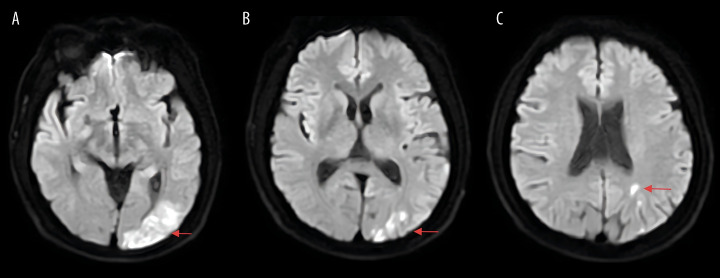

BACKGROUND Conventional clinical understanding holds that venous thrombus formation typically occurs days after traumatic injury. However, our findings demonstrate that acute thrombosis can begin within 7.5 hours after fracture in knee trauma cases, challenging existing paradigms. CASE REPORT A 43-year-old man was admitted to the Emergency Department (ED) after an electric bicycle accident precipitated by acute-onset dizziness accompanied by visual disturbances. Initial radiographic evaluation confirmed a comminuted right proximal tibia fracture with concomitant multiple acute ischemic cerebral infarctions on neuroimaging. Compression ultrasonography performed in the ED showed no evidence of deep venous thrombosis in the lower extremities. However, markedly elevated D-dimer levels (9.39 mg/L; reference <0.5 mg/L) prompted high clinical suspicion for occult venous thromboembolism. Serial Doppler ultrasound surveillance revealed the rapid development of a free-floating thrombus in the right soleal vein within 7.5 hours after the fracture occurred. CONCLUSIONS This case report documents the exceptionally rapid development of venous thrombosis within 7.5 hours following a proximal tibia fracture, particularly in high-risk patients with comorbid conditions such as diabetes mellitus and ischemic stroke. These findings necessitate immediate reassessment of current thromboprophylaxis protocols in orthopedic trauma, emphasizing the critical importance of early and frequent vascular monitoring (including serial Doppler ultrasonography and D-dimer assessment) to detect hyperacute thrombus formation. Clinicians must maintain heightened awareness of this emergency thromboembolic risk while simultaneously managing hemorrhage concerns, as this case demonstrates that the traditional 24-hour prophylaxis window may be inadequate for certain high-risk trauma populations.